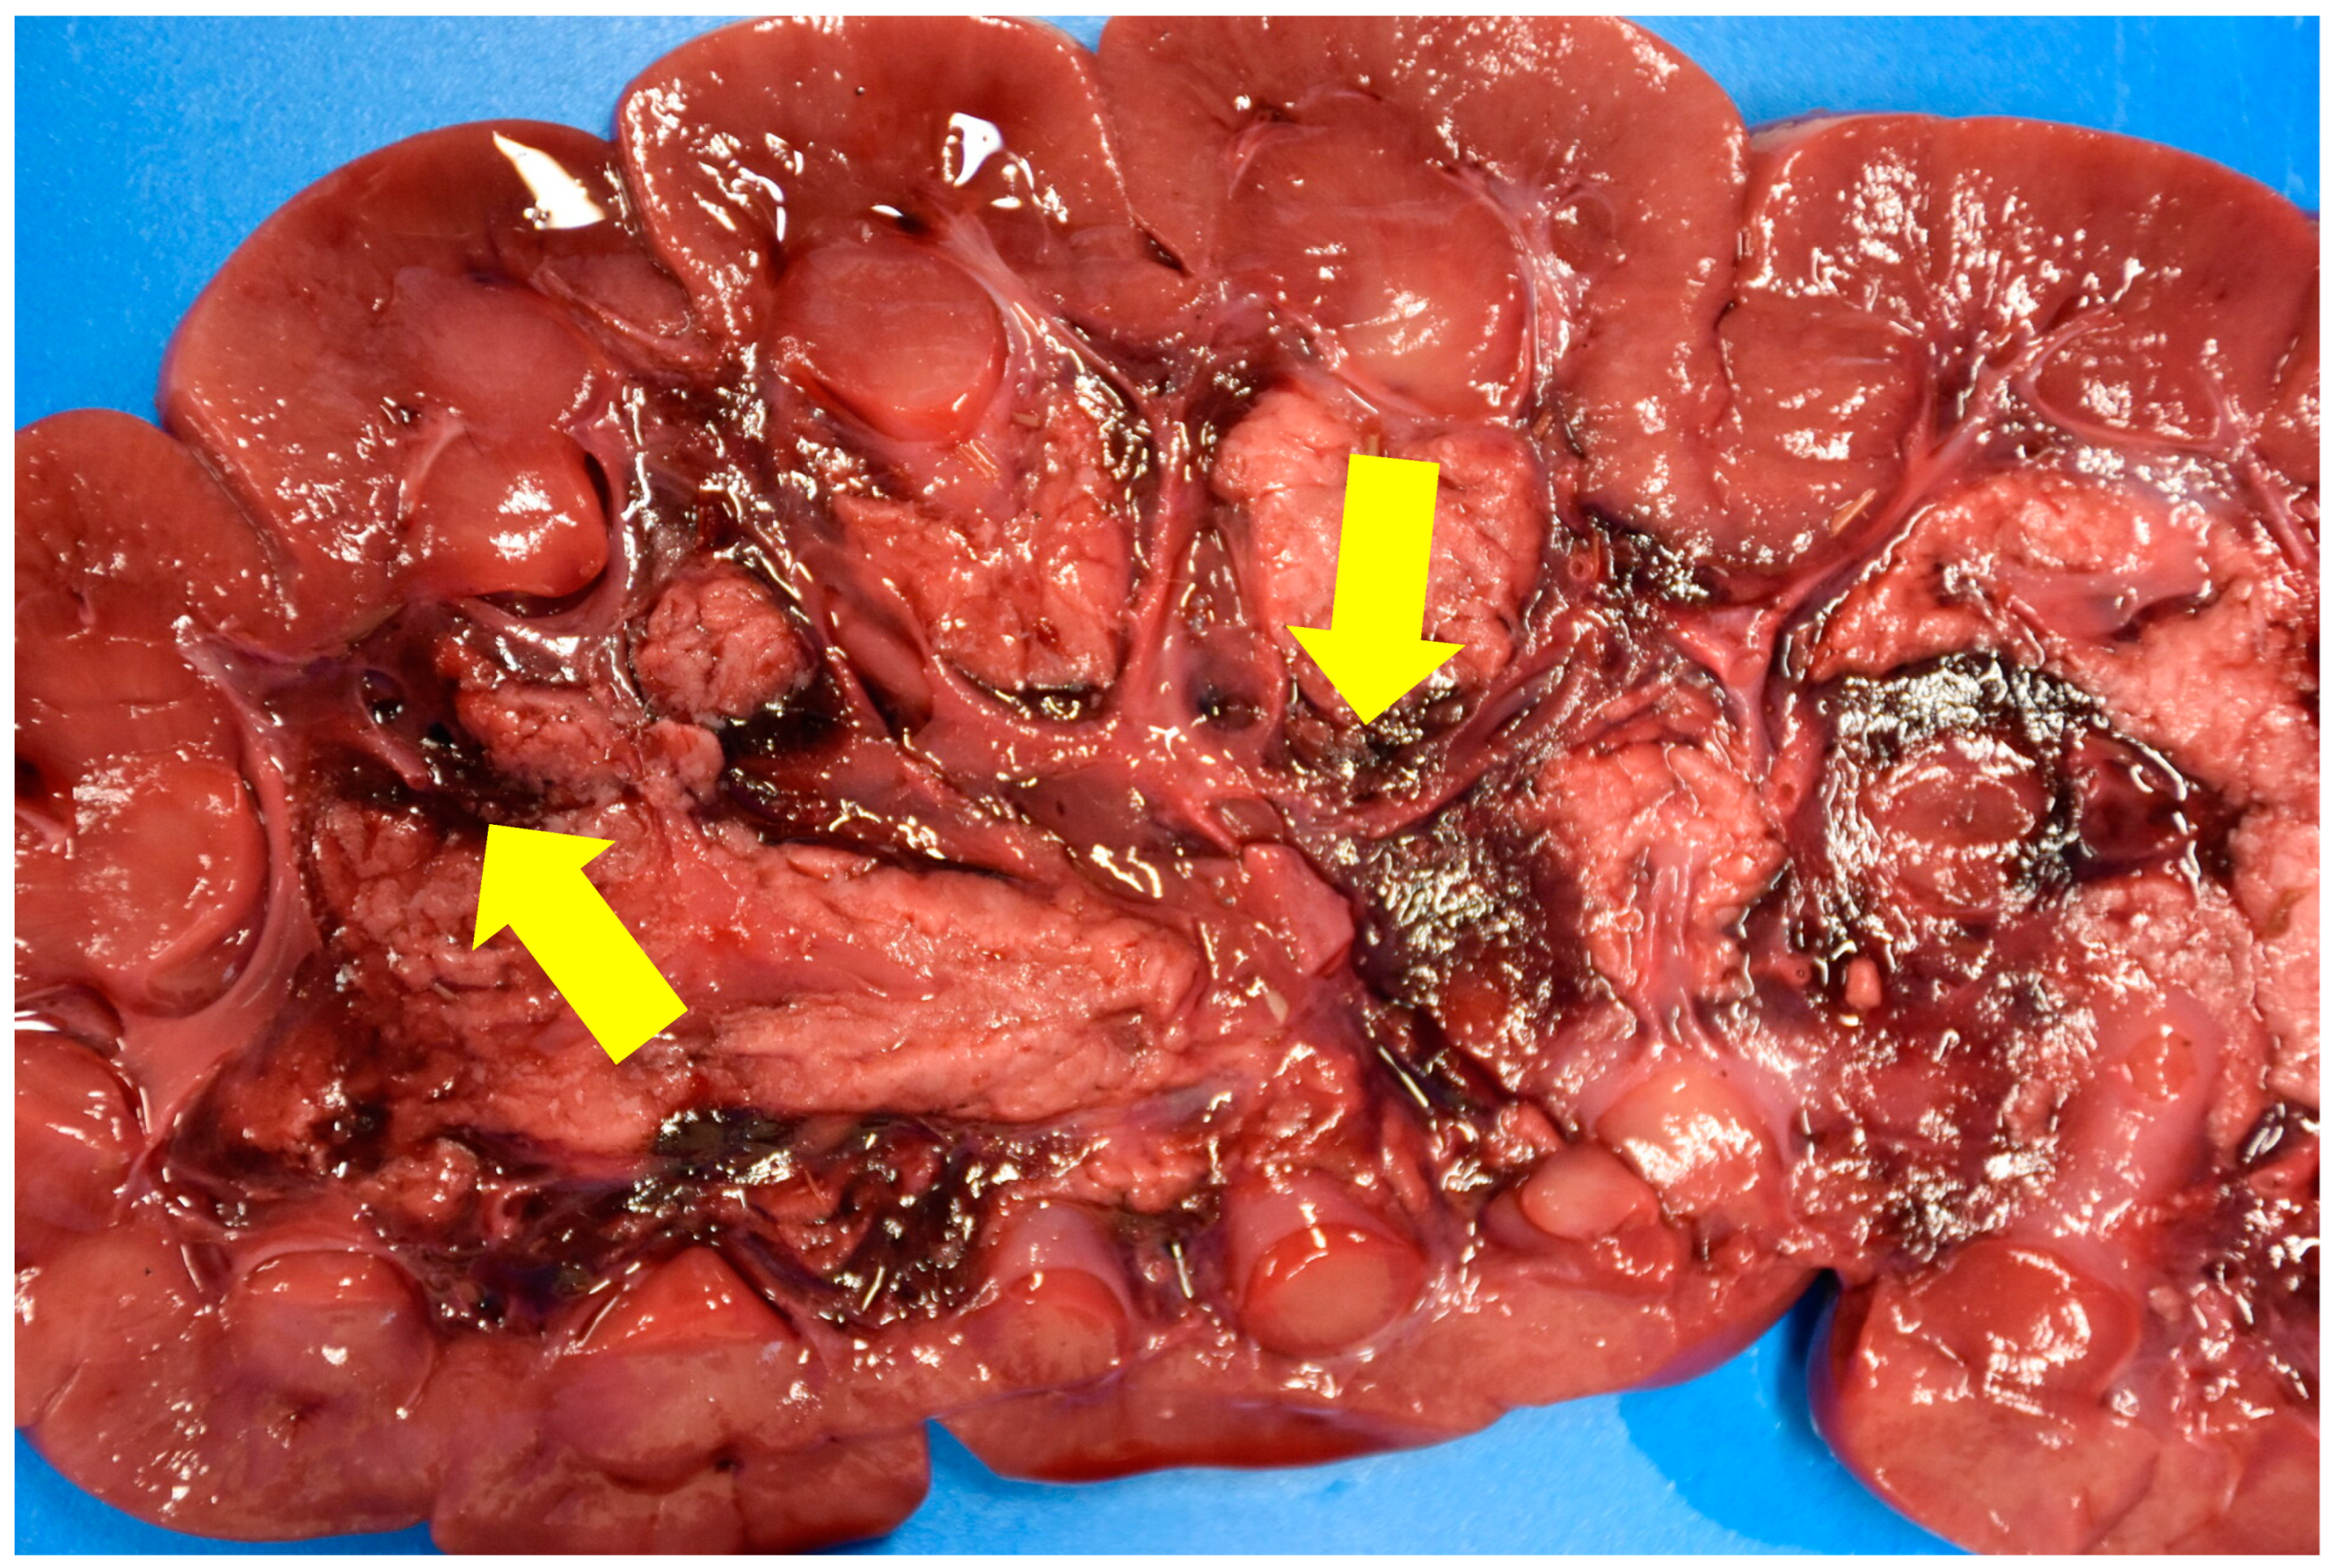

The other lesion systematically observed was a haemorrhagic zone at the junction between the medulla and the calyces/pyelic cavities in the renal interstitial tissue (Figure 2). These lesions were severe and involved both kidneys.

Tannic acids precipitate proteins on the cell membranes in the digestive tract, and cause erosion and ulcerations, in turn altering the absorption (injured mucosa) [5,19]. It can also increase vascular permeability [2] and edema, ascites, pleural or pericardial effusions may be observed, some containing several tens of liters of fluid [6]. The liver can also be affected [3,19]. The most characteristic lesion of this intoxication is the hemorrhage observed between the medulla and the calyces/pyelic cavity of the kidney. Microscopic examination allows a definite diagnosis to be made when tubular necrosis is observed [5,6]. The toxic compound causing these renal tubular necroses is gallic acid [19]. The suspected pathogenesis is a combination of tannin components with cell membrane proteins or nutrients, causing the cell to become necrotic, with these protein compounds then accumulating in the renal tubules [2]. All of the cattle examined at necropsy had these lesions. The microscopic examination provided a definitive diagnosis of these animals, revealing tubular necrosis. For cattle n°3, there is still doubt as to whether he suffered from acorn poisoning, as none of the animals in his herd have been autopsied and diagnosed, and there is no in vivo test to confirm acorn poisoning.

Figure 2. Kidneys of calf n° 6. Hemorrhagic areas can be seen at the junction between the medulla and the calyces/pyelic cavities (yellow arrows) as well as a pitted appearance of the cortex.